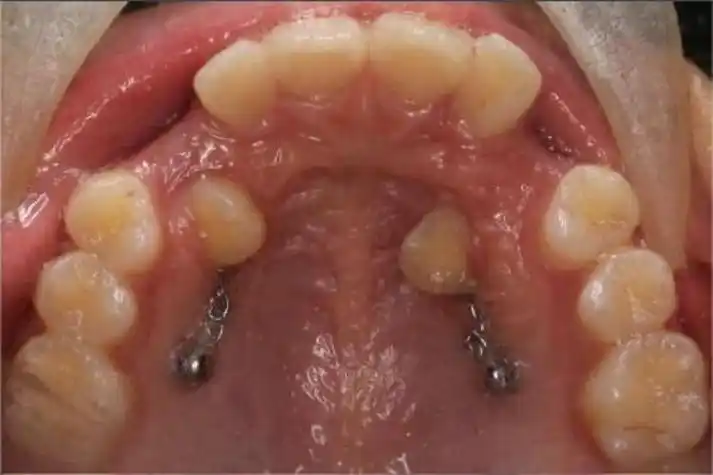

929292上颌尖牙是除第三磨牙外最易阻生的恒牙,患病率为1%-3%

上颌阻生尖牙第一类图